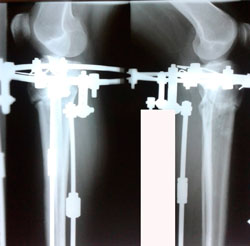

Дата операции 23.03.2020

Дата снятия аппаратов - 07.07.2020

image-07-07-20-04-32-5.jpg

image-07-07-20-04-32-4.jpg